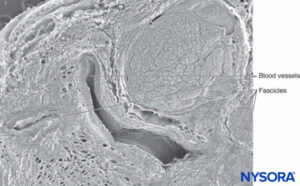

FIGURE 2. Scanning electron microscopy image of the human tibial nerve fascicles and adipose tissue that between fascicles.

Magnification ×75. (Reproduced with permission from Wikinski J, Reina MA, Bollini C, et al: Diagnóstico, prevención y tratamiento de las complicaciones neurológicas asociadas con la anestesia regional periférica y central. Buenos Aires: Panamericana Ed; 2011.)